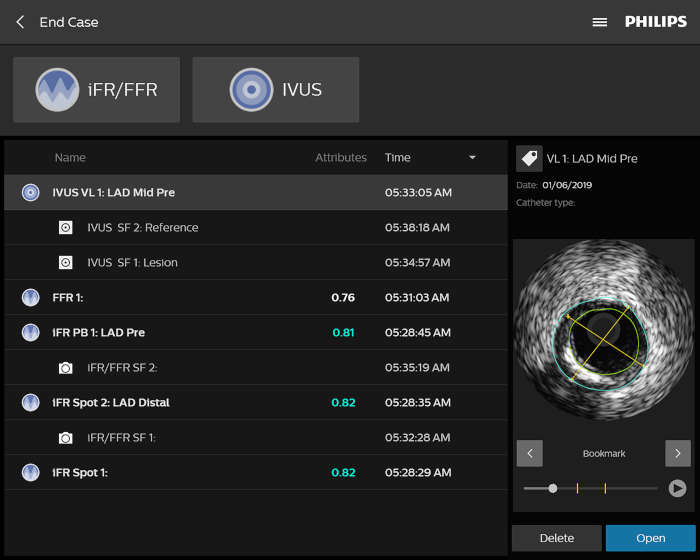

A medida que aumenta el número de pacientes cardiovasculares y vasculares, también lo hace la necesidad de trabajar de forma más inteligente y rápida. Philips IntraSight le ofrece estas herramientas intervencionistas, las mejores de su clase, que le permiten ver con claridad para poder tomar decisiones clínicas rápidas e informadas que pueden conducir a planes de tratamiento óptimos. La integración de la más avanzada plataforma de fisiología e imagenología en su flujo de trabajo debe ser inteligente, sencilla y constante. IntraSight es la única plataforma intervencionista que: Para los clientes con suites intervencionistas que no son de Philips, IntraSight 7 ofrece una integración constante y un uso completo de nuestras aplicaciones de intervención. IntraSight 7 promueve una gestión mejorada del flujo de trabajo con el módulo de pantalla táctil junto a la mesa que permite la facilidad de uso y el acceso a las mejores herramientas intervencionistas de su clase, como iFR/FFR, IVUS y el corregistro. Además, la integración de IntraSight 7 con las suites intervencionistas que no son de Philips permite a los clientes beneficiarse de soluciones intuitivas como, por ejemplo, la mejora de los vasos y la detección de dispositivos, lo que, en última instancia, permite a todos los clientes beneficiarse de la oferta integral de soluciones inteligentes de IntraSight 7 sin compromiso.

Presentamos la nueva plataforma de aplicaciones intervencionistas Philips IntraSight, en la que la imagen, la fisiología, el corregistro* y el software se unen para facilitar una atención óptima del paciente. IntraSight ofrece un conjunto completo de modalidades clínicamente probadas, como la iFR/FFR, la IVUS y el corregistro* para simplificar las intervenciones complejas, acelerar los procedimientos rutinarios y proporcionar una mejor atención al paciente.

Construida sobre una plataforma inteligente basada en aplicaciones que puede escalar para satisfacer las necesidades cambiantes de su laboratorio cuando se disponga de nuevas aplicaciones o modalidades, sin necesidad de adquirir nuevo hardware. Solo Philips IntraSight ofrece las mejores herramientas de imagenología y fisiología de su clase con iFR, corregistro iFR*, FFR, IVUS, corregistro IVUS* y Angio+*. Con su arquitectura modular, IntraSight se mantiene a la vanguardia de los últimos avances y actualizaciones de seguridad importantes.

IntraSight es simple

Ofrece una experiencia de usuario excepcional con una interfaz moderna e intuitiva que minimiza las curvas de aprendizaje y aumenta la confianza del flujo de trabajo.

Fácil de usar porque le permite: